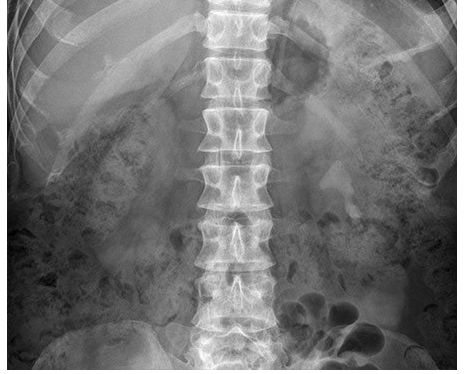

This abdominal X-ray demonstrates multiple dilated loops of bowel with clear valvulae connivente markings. The large bowel is collapsed. **This indicated small bowel obstruction.**